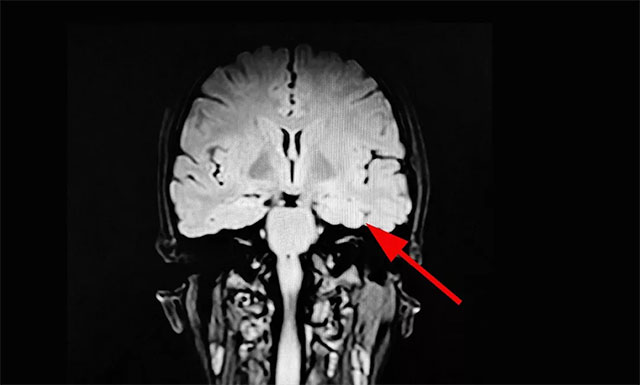

▲ 综合多种检查,最终确定患者癫痫病灶

经过系列检查,玲玲被确诊为难治性癫痫,系统内科药物治疗不佳,影像学、24小时长程视频脑电监测并结合患者临床病史最终定位致癫灶,手术指征明确,未见明显手术禁忌。在征得家属同意后,杨忠旭教授在助手杜立功协助下以及崔丽华主任脑电监测辅助下成功为患者进行了手术。目前玲玲已康复出院。